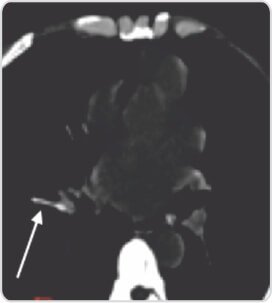

থোরাক্সের সিটি স্ক্যান করা হয়েছিল যা ডান অবরোহী পালমোনারি ধমনীর অগ্রবর্তী সেগমেন্টাল শাখায় ক্যানুলা টিপটি বিচ্ছিন্ন হয়ে গেছে। IV ক্যানুলা শ্যাফ্ট অপসারণের জন্য রোগীর কার্ডিওথোরাসিক অস্ত্রোপচারের পরিকল্পনা করা হয়েছিল। অস্ত্রোপচারের আগে, ইন্টারভেনশনাল রেডিওলজিস্টের মতামত নেওয়া হয়েছিল, এবং রোগীকে ফ্লুরোস্কোপি নির্দেশিত অপসারণের জন্য নেওয়া হয়েছিল।

ফ্লুরোস্কোপিক গাইডেন্সের অধীনে, ক্যানুলার ডগাটি ডান অবরোহী পালমোনারি ধমনীর পূর্ববর্তী সেগমেন্টাল শাখায় একটি রৈখিক ফিলিং ত্রুটি হিসাবে চিহ্নিত করা হয়েছিল। পরের দিন রোগীকে ছেড়ে দেওয়া হয়

রৈখিক হাইপারডেন্স ফরেন বডি ডান অবরোহী ফুসফুসীয় ধমনীর অগ্রবর্তী সেগমেন্টাল শাখায় উদ্ভাসিত